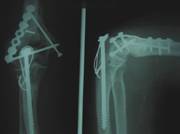

of surgical reduction. Fig 1 & 2

Fig.1

Type C2 Fracture

Fig.1A:

Pre operative Radiograph Fig 1B:Immediate

post operative

Fig

1 C:After 6 months

Fig .

2. Type C1Fracture

Pre operative

Radiograph

Immediate post operative

After 6 months